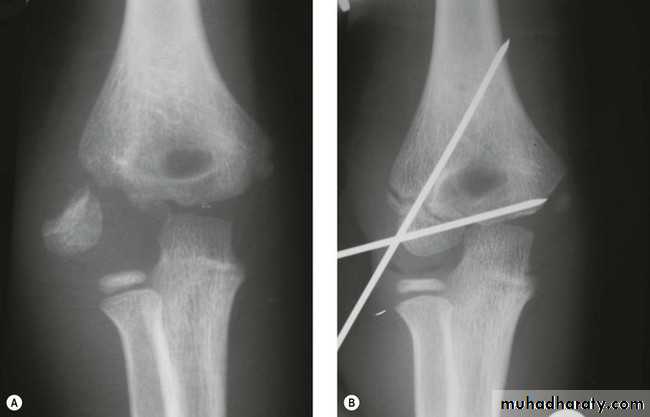

Conservative management

Initially, closed reduction is tried under general anesthesia by traction and counter traction methods .The medial and lateral tilt is corrected first and posterior displacement next.

An immediate check can be made whether the reduction has been successful by noting the long axis of the forearm and arm, which should be parallel.

Any deviation from the normal indicates residual uncorrected deformities. Two to three attempts under the same anesthesia can be made and the elbow is immobilized in hyper flexion, as in this position the triceps acts as an internal splint and the forearm is pronated as in this position the medial periosteal hinge closes the cortex laterally.

Check radiograph is taken and all the angles so far discussed should be restored to normalcy, failure of which requires considering alternative methods of treatment like skeletal traction or open reduction and internal fixation.

Surgery

This includes PCIF or open reductionClosed reduction and percutaneous fixation (PCIF): In cases where hyper flexion of the elbow cannot be done due to gross swelling in and around